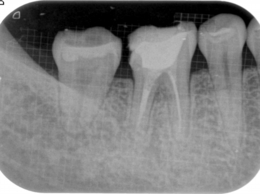

初診時のレントゲン写真

写真の右から2本目の歯の違和感でいらっしゃいました。

CT撮影すると、炎症は上顎洞にも波及しています

このように、通常のレントゲンだけでは炎症による病変の範囲等がわかり難い場合はCT撮影も行います。